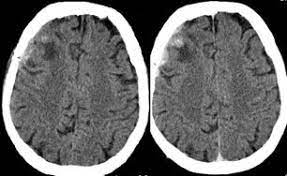

El método diagnóstico de elección para demostrar la presencia de sangre en el espacio subaracnoideo es la tomografía computarizada de la cabeza sin medio de contraste intravenoso. La tomografía (con angiografía) computarizada se utiliza para confirmar una hemorragia subaracnoidea y buscar su origen. Es más rápida y sensible que la resonancia magnética para reconocer la hemorragia en las primeras 24 horas. La tomografía computarizada revela sangre en las cisternas basales en las primeras 12 horas con aproximadamente un 95% de sensibilidad y especificidad.